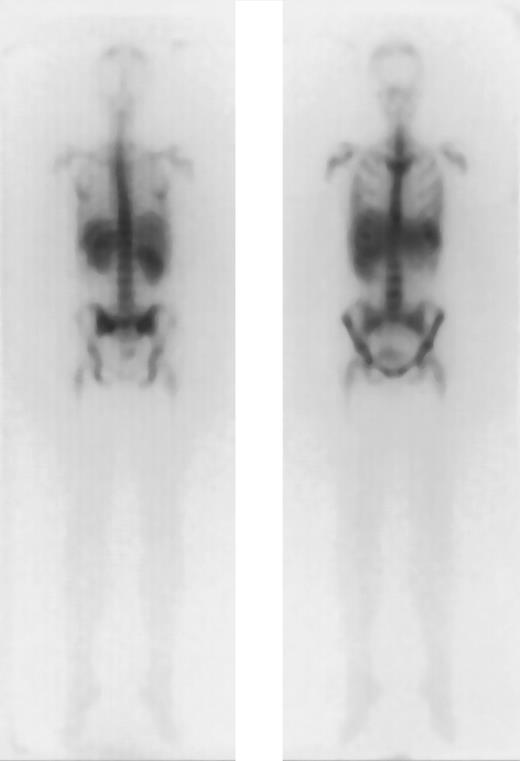

Favorable dosimetry in a patient with AML in PR (unique patient number 664).

Biodistribution of 1 mg 188Re-labeled anti-CD66 monoclonal antibody after 40 hours, in anteroposterior and posteroanterior projection.

The results of dosimetry for some of these patients have been previously published.37 The tracer dose consisted of 1 to 2 mg anti-CD66 antibody labeled with 1.2 ± 0.6 GBq188Re. The application of the tracer dose was tolerated without any significant reaction by all 36 patients. All of these patients had a favorable dosimetry as defined above and proceeded to transplantation. For therapy a mean of 11.1 ± 2.2 GBq was injected in 1 to 2 fractions. A typical example is given in Figure1. The detailed results of dosimetry are shown in Figure 2 and Table2. The total doses shown in Table 2include the radiation exposure due to the dosimetric dose. The mean red marrow dose achieved was 15.3 ± 4.8 Gy, and the median dose was 14.9 Gy, ranging from 8.1 to 28 Gy. The kidney was the normal organ receiving the highest dose in 22 patients; the liver in 10 patients; and equivalent doses to kidney and liver were observed in 4 patients. Thus, the radiation absorbed doses were red marrow, 1.5 ± 0.6; spleen, 1.6 ± 1.3; liver, 0.5 ± 0.2; kidney, 0.7 ± 0.2; and lung, 0.1 ± 0.1 Gy/GBq. These values therefore give the following marrow:organ ratios: marrow:liver, 3:1; marrow:kidney, 2.1:1; and marrow:lung, 15:1. We observed no significant differences between the marrow doses of patients in complete remission and those in PR. The acute toxicity of the therapeutic antibody application was very mild, with two-thirds of patients complaining of mild nausea; no episodes of severe toxicity were observed.